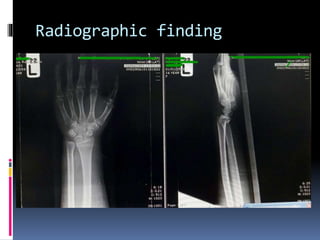

Radiographic finding

 Distal end radius fracture volar displacement

& dorsal angulation ( Smith ‘s fracture )

X-Ray Finding

 Fractures of the distal radius with associated

palmar angulation of the distal fracture

fragment. Classically, these fractures are extra-

articular transverse fractures and can be thought

of as a reverse Colles fracture.